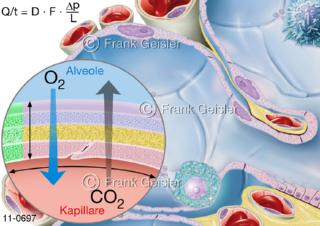

11-0697 Lungenbläschen Alveolus mit Darstellung Diffusion, Ficksches-Gesetz